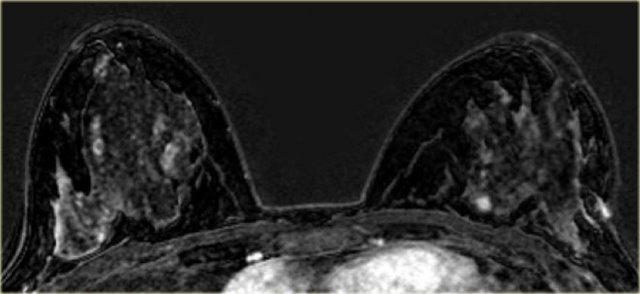

Bên trái là bệnh nhân có các vùng ngấm thuốc không tạo khối ở cả hai vú (DCIS).

Có một khối ngấm thuốc nhỏ ở phía trong vú trái, được xác định là ung thư xâm lấn nhỏ.